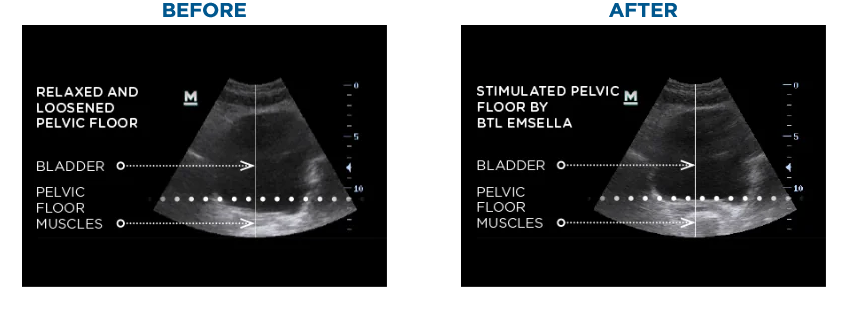

Here are unretouched images of an unstimulated, relaxed, loosened and mixing bowl-shaped pelvic floor (left) and the same pelvic floor having its doorbell rung by an electromagnetic Emsella pulse. Note how the floor has risen up to the dotted line and looks more like a saucepan (right). If I was a judge in the Olympic Pelvic Floor Reverse Pullup and Cooking Ware event I would for sure give the Emsella a 9.5 and maybe even a 10. I also think Julia Child would agree with me, for what it’s worth.